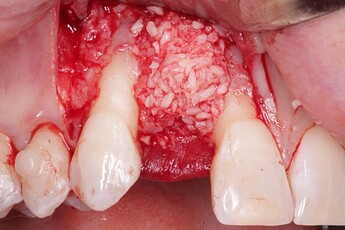

An implant was placed in site #7 with an existing buccal bone defect (Pictures 1 & 2). Prior to placing the bone graft over the implant, the membrane is measured and trimmed and tucked under the palatal flap trying to avoid wetting the entire membrane (Picture 3). The particulate bone graft (DALI Classic Cortical Cancellous Mix) is placed over the implant surface to restore the defect (Picture 4). The membrane is folded over the crest and onto and slightly beyond the particulate bone graft while slowly dropping saline onto the membrane (Picture 5). This enables the membrane to contour and drape over the graft and “seal” the graft off from the surrounding soft tissue (Picture 6 and 7). Sutures are then used to achieve primary closure over the GBR site (Picture 8).

Pic 4

osseoseal-4